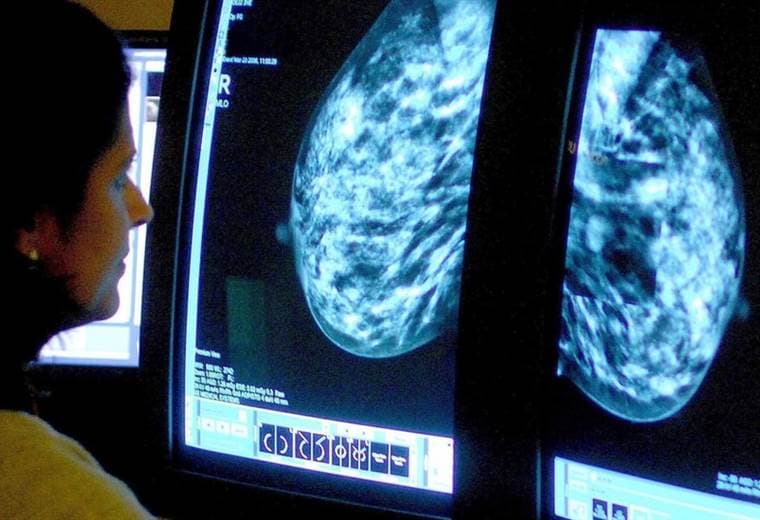

La mujer de Florida (sureste de EE.UU.) fue diagnosticada con un cáncer de mama avanzado, que se había esparcido por su cuerpo y que no podría tratarse con terapia convencional.

Tenía tumores del tamaño de una pelota de tenis en su hígado y formaciones en otras partes.

El tumor de un paciente se analiza genéticamente para identificar los cambios que hacen que el cáncer sea visible para el sistema inmunitario.

De las 62 anomalías genéticas en Perkins, solo cuatro fueron líneas de ataque potenciales.